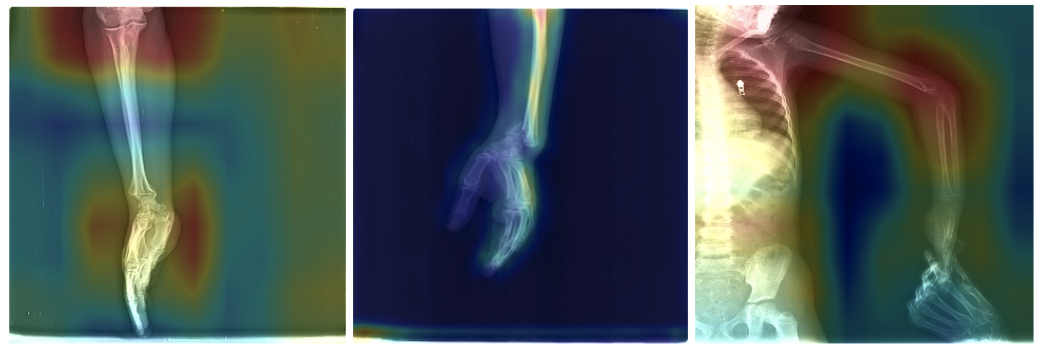

On medical imagery, often images are being annotated or contains a scale. Below in another example of a model focusing on the annotations instead of the actual region of interest.